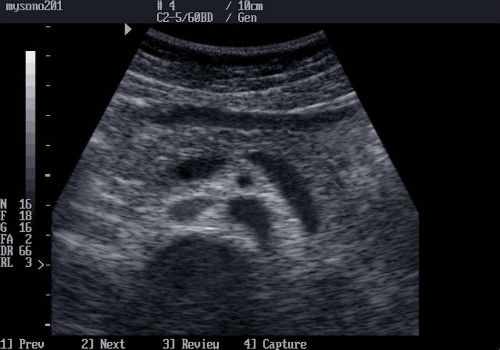

При обследовании железы на УЗИ, эхогенность ее сравнивается в качестве нормы, с тем же уровнем в области печени. В норме поджелудочная железа должна быть несколько светлее, чем печень и иметь четкий ровный контур. Если расшифровка при узи выявляет неровные края с зазубренной поверхностью, и размытый силуэт органа, то это может означать, что эхогенность повысилась и имеет место быть патологическое нарушение структурности и функциональности органа.

Например, если эхогенность повышена, изображение органа будет более светлым, чем необходимо. А значит, структура органа стала более плотной, что говорит о хроническом воспалении. При снижении эхогенности изображение будет более темным, что свидетельствует об отеке или остром воспалительном процессе.